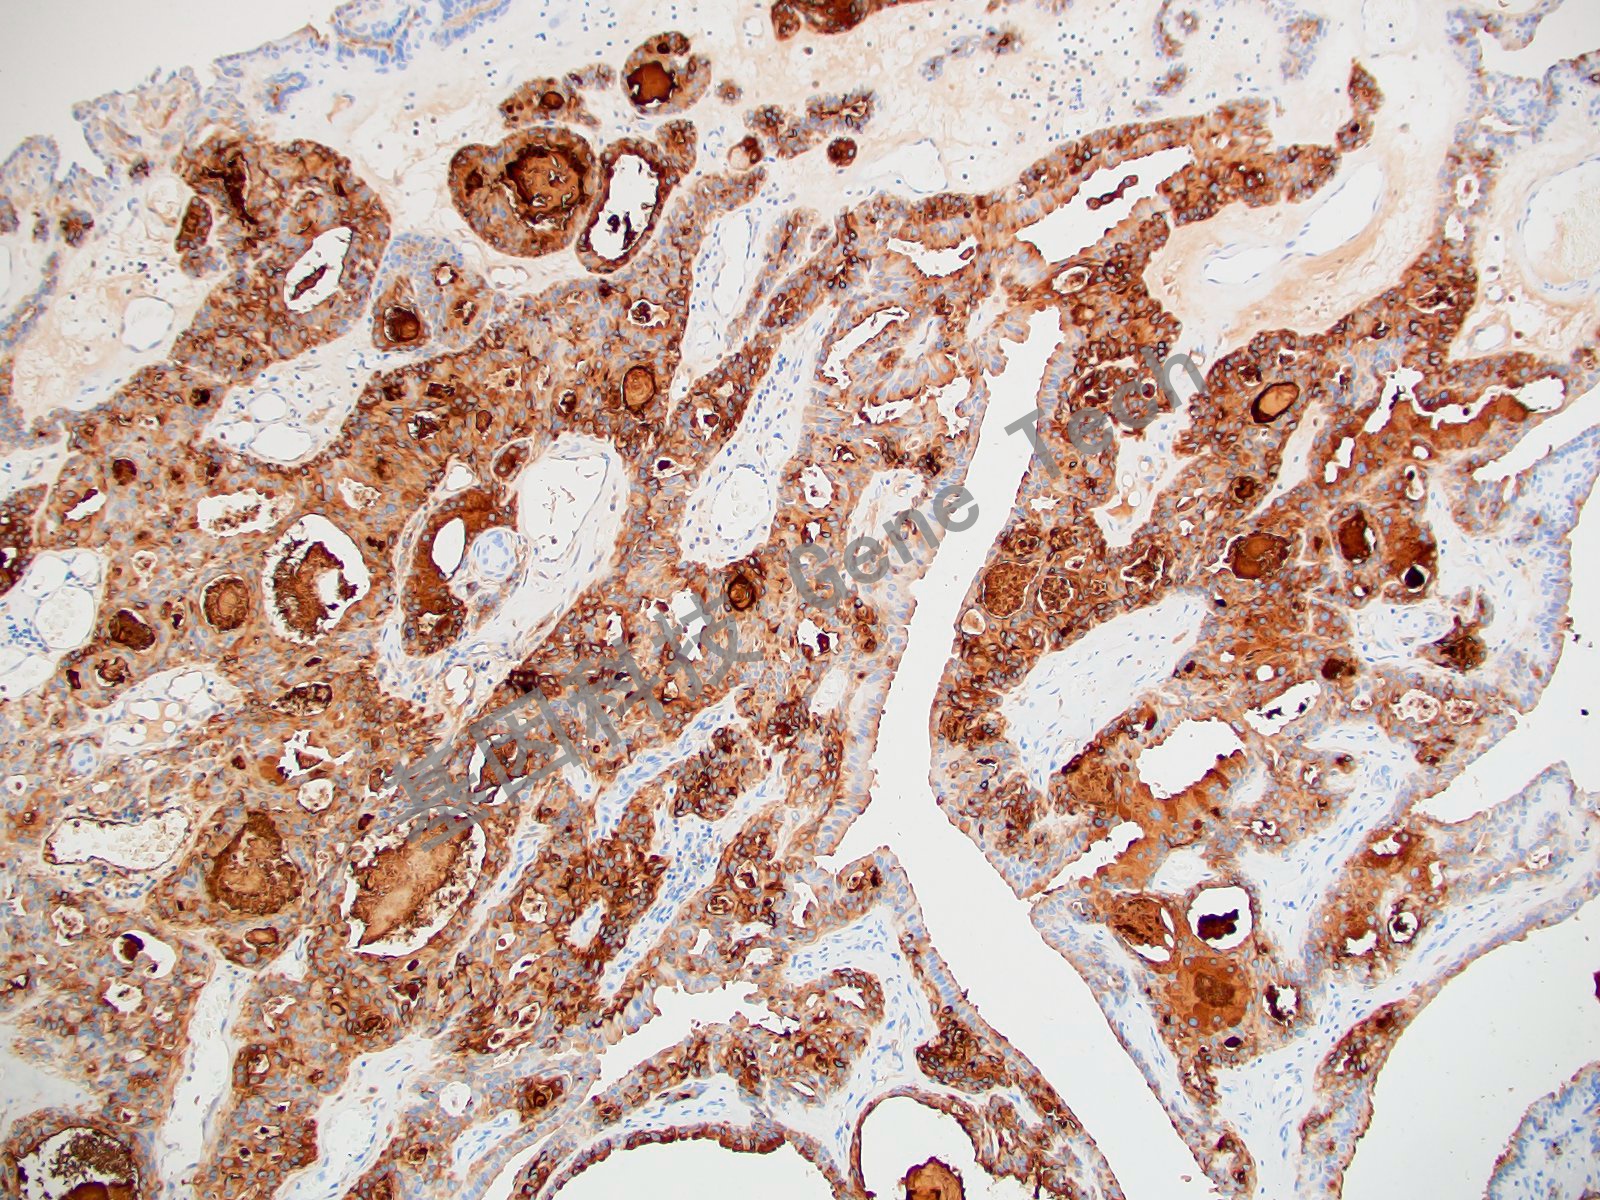

乳腺癌石蜡切片,用 Survivin(GT2048)染色,细胞浆/细胞核阳性,DAB 显色。